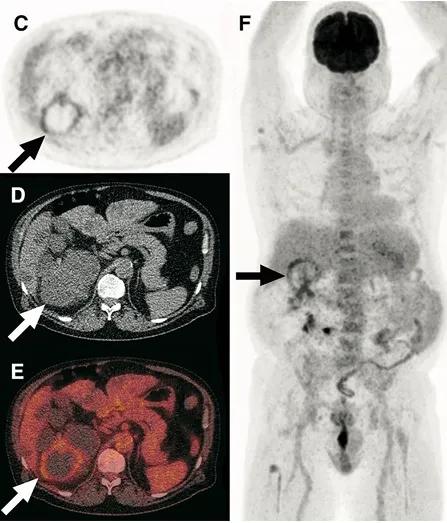

A DRPAD não é contraindicação à DP — e, na prática, muitos pacientes têm resultados comparáveis à hemodiálise. O “porém” está na mecânica: rins/hepatomegalia podem reduzir tolerância a volumes, aumentar risco de hérnias e extravasamentos, e piorar desconforto respiratório. Com técnica adequada (cateter presternal ou lateral, volumes menores, cicladora noturna e decúbito supino), a maioria das barreiras é contornável. Neste post, revisamos quando a DP é ótima, quando exigir cautela e como ajustar a prescrição para segurança e qualidade de vida.